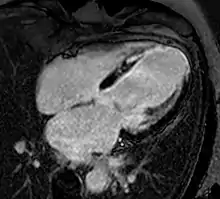

Enlarged right ventricle with poor function in a patient with repaired tetralogy of Fallot by CMR